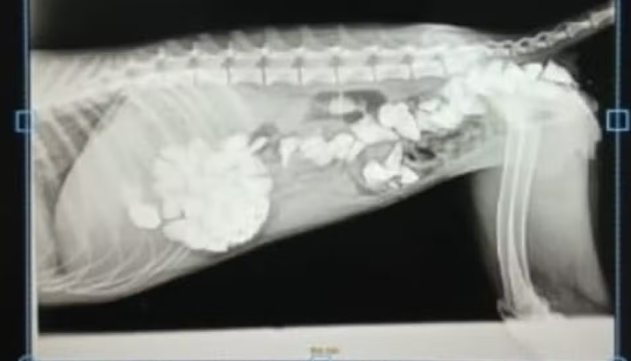

Raio-x da cachorra Xena mostra pedras no estômago — Foto: Arquivo pessoal/Fernanda Vieira

Uma situação comovente veio à tona após o resgate de uma cachorra em Palmas, capital do Tocantins. Segundo informações do g1 Tocantins, a cadelinha, agora chamada de Xena, foi encontrada em um terreno na região sul da cidade, sem conseguir se movimentar. De acordo com a veterinária Fernanda Vieira, diretora de saúde animal da Secretaria de Proteção e Bem-Estar Animal de Palmas (Sedem), o animal estava com o estômago e intestino cheios de pedras, que teria engolido ao tentar saciar a sede lambendo água misturada às britas do chão.

“Ela estava deitada, lambia as pedras tentando beber água e acabou ingerindo os pedregulhos. No dia em que chegou à clínica, chegou a defecar pedras. Uma cena muito triste”, relatou a veterinária.